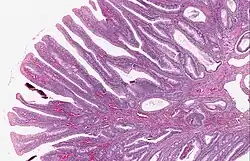

Tubulovillous adenoma 20% to 25%[15] 25–75% villous[14]

Villous adenoma 15%[16] to 40%[15] Over 75% villous[14]

The common adenomas of the colon (colorectal adenoma) are the tubular, tubulovillous, villous, and sessile serrated (SSA).[18] A large majority (65–80%) are of the benign tubular type with 10–25% being tubulovillous, and villous being the most rare at 5–10%.[9]

The villous subdivision is associated with the highest malignant potential because they generally have the largest surface area. (This is because the villi are projections into the lumen and hence have a bigger surface area.) However, villous adenomas are no more likely than tubular or tubulovillous adenomas to become cancerous if their sizes are all the same.[18]